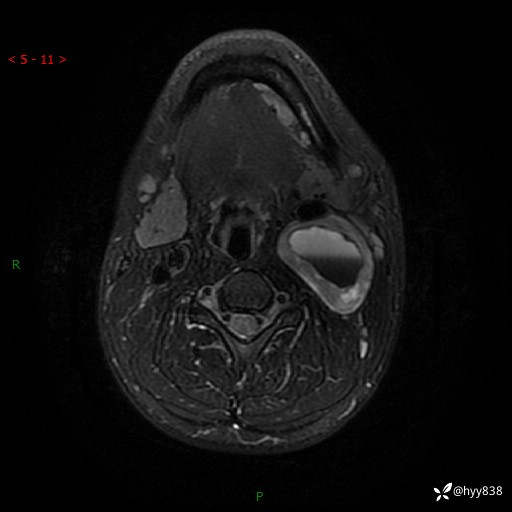

年轻小伙,发现左侧颈部肿物3年余,逐渐增大---结果公布~

现病史:患者约3年前因感冒发现左侧颈部长一肿物,约半个鸡蛋大小,无明显疼痛及其他不适,一直未行特殊处理。3个月前发现左侧颈部肿物变大,随后至当地市第二人民医院耳鼻喉科行左侧颈部彩超示:左侧颈部囊实混合性包块;喉部MPR示:左侧胸锁乳突肌内前方占位,累及左侧喉旁间隙,建议增强扫描。建议手术治疗。患者考虑。随后至我院肿瘤科就诊,行细胞学穿刺示:考虑血管源性肿瘤可能,建议进一步检查。建议至我院口腔科就诊,行颌面部MRI示:左侧颌下腺后方团状异常信号灶,建议增强。建议手术治疗。为求进一步治疗,门诊以“左侧颈部肿物”收入院。 起病以来,患者神志清、精神良好,饮食睡眠良好,大小便正常,体重未见明显变化。

颈部MRI平扫+增强